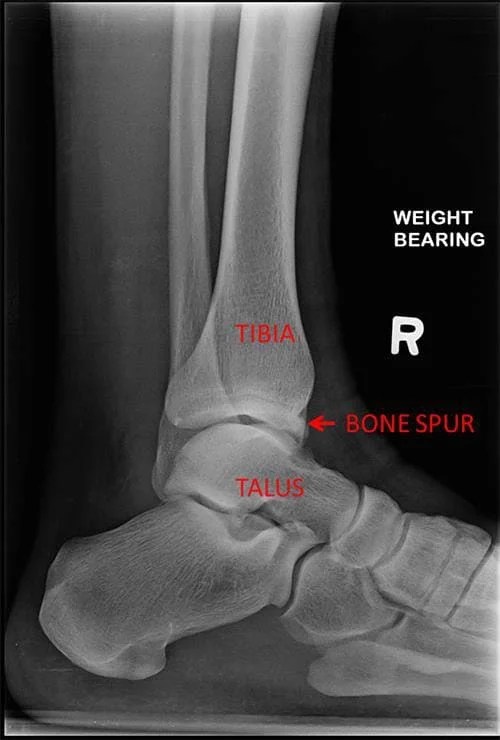

Arthritis And Bone Spurs In Ankle . In about 90% of cases, ankle osteoarthritis causes are past traumas, compared to 2% to 10% of knee oa cases. Osteoarthritis breaks down connective tissue. The surgeon can see the affected bone inside your foot or ankle and will be able to perform a procedure called debridement. Joint damage from osteoarthritis is the most common cause of bone spurs. This can result in bone rubbing on bone and produce painful osteophytes (bone spurs). This can cause stiffness, swelling, and pain in the joint. An ankle injury can damage cartilage directly, make the joint less stable or. This article will go over what you should know about ankle osteoarthritis, including the symptoms of ankle osteoarthritis, how osteoarthritis in the ankle is diagnosed, and treatment for ankle osteoarthritis. In addition to age, other risk factors for osteoarthritis include obesity and family history of the disease. In this, they’ll use small tools to remove any bone spurs and clean the area inside. Bone spur removal for ankle arthritis, a procedure called anterior ankle exostectomy, may be a surgical option for patients with arthritis. Osteoarthritis of the ankle happens when the cartilage between the bones wears down.